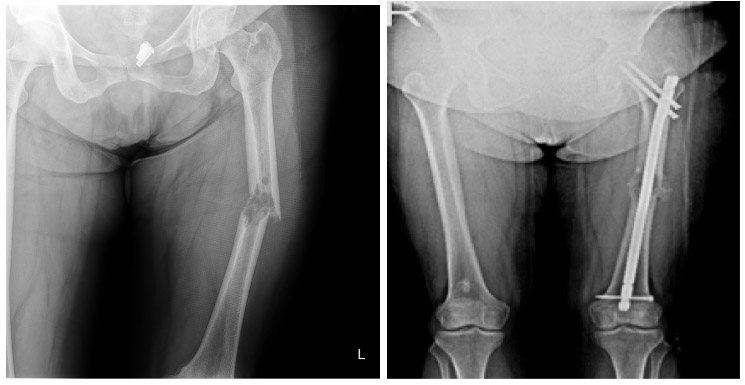

Before and after surgery: The X-ray shows a destructive and displaced fracture in the mid-section of the left femur, with fixation of the fracture in the correct position using a nail.